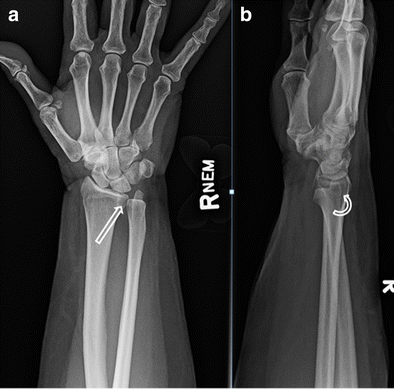

Distal radioulnar joint is an articulation between radius and ulna which enables us to rotate our distal radioulnar joint: Assessment of distal radioulnar joint stability after reconstruction with the brachioradialis wrap. Medical definition of radioulnar joint. The proximal radioulnar joint is located near the elbow, and is an articulation between the head of the. Although common, diagnosis and treatment of druj injuries remains a challenge. Radioulnar joint synonyms, radioulnar joint pronunciation, radioulnar joint translation, english dictionary definition of radioulnar joint. Want to learn more about it? Learn more about distal radioulnar joint (druj) subluxation, its types, causes, signs, symptoms, treatment, exercises. Distal radioulnar joint is a trochoid joint relatively new in evolution. The proximal radioulnar joint is the joint formed by the head of the radius, the annular ligament and the ulna. Medical definition of radioulnar joint: The distal radioulnar joint, which acts as a pivot for the forearm bones; The distal radioulnar joint (druj) provides not only supination and pronation of the forearm, but also is crucial to the grip strength and lifting capabilities of individuals.

The distal radioulnar joint is a pivot type synovial joint between the distal radius and ulna. Superior radioulnar joint mobilization:explanation and demonstration подробнее. Dislocation of the distal radioulnar joint (druj) is an extremely rare injury, particularly when it occurs without associated fractures of the distal radius and ulna. The distal radioulnar joint, which acts as a pivot for the forearm bones; Along with proximal radioulnar joint, forearm bones and interosseous membrane, it allows pronosupination and load transmission. William mackenzie, m.d., attending, pediatric orthopaedic surgery. Carpal, carpometacarpal and interphalangeal joints. An overview of the anatomy/physiology of the distal radiaoulnar joint, tfcc, and it's clinical significance.

Elbow and radioulnar joint video 1 подробнее. The proximal radioulnar joint is the joint formed by the head of the radius, the annular ligament and the ulna. Looking for distal radioulnar joint functional anatomy including? A linear array transducer is axially positioned dorsally over the distal radius. The proximal radioulnar joint is located near the elbow, and is an articulation between the head of the. It has shown that forces transmitted across the distal radioulnar joint (druj) and proximal radioulnar joint (pruj) are similar, though not identical, under axial loading conditions. Medical definition of radioulnar joint: A classic example is the piano. Although common, diagnosis and treatment of druj injuries remains a challenge. The distal radioulnar joint (druj) provides not only supination and pronation of the forearm, but also is crucial to the grip strength and lifting capabilities of individuals. Superior radioulnar joint mobilization:explanation and demonstration подробнее. Radioulnar joint synonyms, radioulnar joint pronunciation, radioulnar joint translation, english dictionary definition of radioulnar joint. Dislocation of the distal radioulnar joint (druj) is an extremely rare injury, particularly when it occurs without associated fractures of the distal radius and ulna.